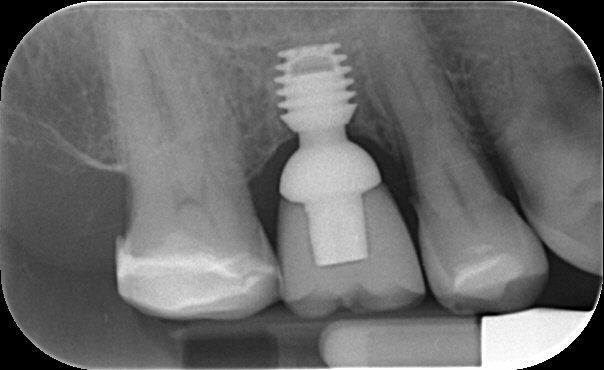

A dental implant is a medical grade titanium rod which is placed into the jaw. It is used to support one or more false teeth. In practice both the false teeth and the supporting rod are known as ‘implants’.

Replacing a missing tooth with a dental implant sounds like a complex treatment. In fact, the process can be simple. Implants are placed into the jaw and left buried for about three months for them to take to the bone in a process known as osseointegration. After this time the implant is uncovered, some measurements taken, and a temporary fixture is fitted. After two or three weeks the permanent restoration resembling the colour and shape of a normal tooth is fixed.

A crown

- involves one tooth only and is made of natural shade white material